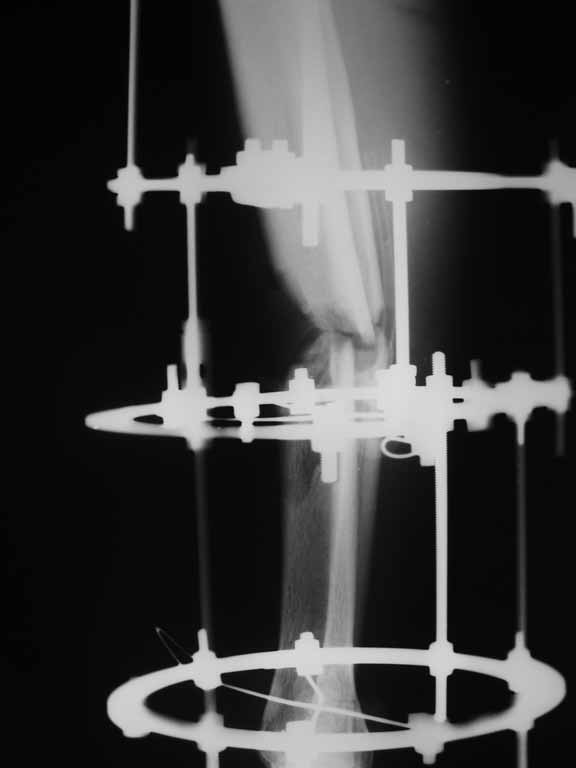

Вот пример, тоже открытый перелом, первичный дефект, пробыл в аппарате 5 мес. Титановый гвоздь, сразу динамический, без покрытия. Больше не делали ничего.